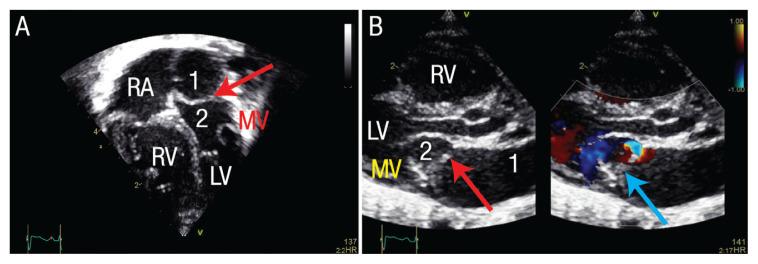

Cor triatriatum sinistrum (CTS) is a rare congenital cardiac anomaly characterised by an abnormal septum within the left atrium impairing blood flow to the left ventricle. We report the case of a two-month-old male infant who presented with symptoms of heart failure since the age of two weeks. He was admitted to a local hospital and was managed with antibiotics because of the impression of pneumonia. Due to persistent unresolved tachypnoea and tachycardia, he was referred to Sultan Qaboos University Hospital, Muscat, Oman, in 2019 for cardiac evaluation which confirmed a diagnosis of isolated CTS with severe stenosis and pulmonary hypertension. He underwent an urgent surgical excision of the membrane with uneventful recovery.

先天性左房三房心(CTS)是一种罕见的先天性心脏畸形,其特征为左心房内异常隔膜,导致血液流向左心室受阻。我们报告了一例两个月大的男性婴儿,他自两周大以来就出现心力衰竭的症状。他被收治到当地医院,由于疑似肺炎,给予了抗生素治疗。由于持续存在的呼吸急促和心动过速未得到解决,他于 2019 年被转诊到阿曼马斯喀特的苏丹卡布斯大学医院进行心脏评估,确诊为孤立性 CTS 合并严重狭窄和肺动脉高压。他接受了紧急手术切除隔膜,术后恢复顺利。